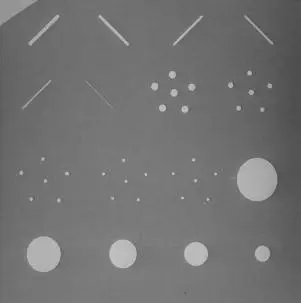

關於乳房攝影的假體影像(如圖),下列敘述何者正確?

圖中顯示乳房攝影 ACR 假體的 X 光影像,內含三排不同類型的模擬測試物(由上而下):

第一排(上方)— 纖維(Fibers):影像上方可見 6 條不同直徑的白色斜線(尼龍纖維),模擬乳腺管中的纖維狀鈣化。纖維直徑從 1.56 mm 到 0.40 mm 遞減,由左上至右方排列,粗細差異明顯。

第二排(中間)— 鈣化點群(Microcalcification Speck Groups):中間區域可見 5 組不同大小的點狀群集,模擬微鈣化(microcalcifications)。每群含 6 個氧化鋁微粒,直徑從 0.54 mm 至 0.16 mm 遞減,越往右群集越不明顯。

第三排(下方)— 腫塊(Masses):下方可見 5 個不同大小的圓形亮區(透鏡狀結構),模擬腫瘤質量(tumor masses)。直徑從最左邊約 2.00 mm 到最右邊 0.25 mm 遞減,大小差異明顯可辨。